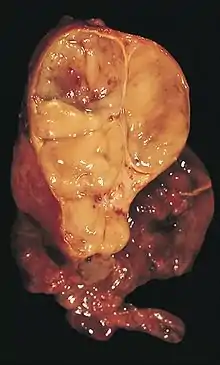

| An encapsulated thymoma (mixed lymphocytic and epithelial type) | |

A thymoma is a tumor originating from the epithelial cells of the thymus that is considered a rare malignancy. Thymomas are frequently associated with neuromuscular disorders such as myasthenia gravis;[1] thymoma is found in 20% of patients with myasthenia gravis.[2] Once diagnosed, thymomas may be removed surgically. In the rare case of a malignant tumor, chemotherapy may be used.

The diagnosis is made via histologic examination by a pathologist, after obtaining a tissue sample of the mass. Final tumor classification and staging is accomplished pathologically after formal surgical removal of the thymic tumor.